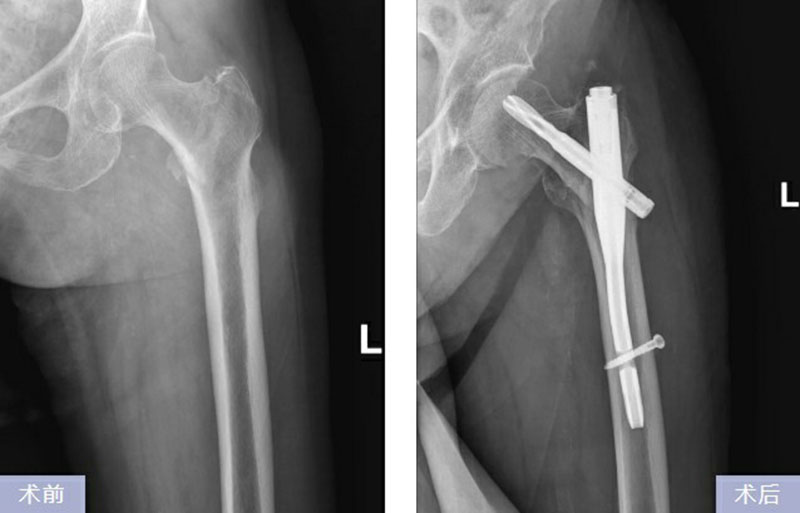

專家們在充分評估手術(shù)安全性、耐受性的基礎(chǔ)上,預(yù)估了術(shù)中、術(shù)后可能出現(xiàn)的意外情況,并制定了詳盡的手術(shù)方案和應(yīng)急預(yù)案,確保手術(shù)的順利進行。經(jīng)過慎重評估,骨外科專家團隊決定實施防旋股骨近端髓內(nèi)釘固定術(shù)(PFNA內(nèi)固定術(shù))。經(jīng)過完善的術(shù)前準(zhǔn)備,骨外科專家為其進行手術(shù)。手術(shù)過程中,韓奶奶未感受到任何痛苦。術(shù)后,在醫(yī)護人員精心治療下,韓奶奶的病情平穩(wěn),目前已步入功能恢復(fù)階段。